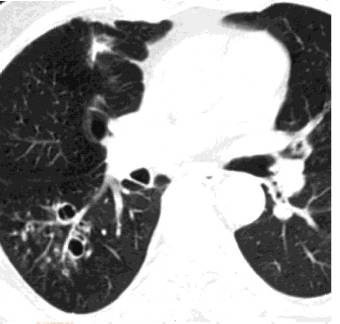

气道侵袭性曲霉菌病,右下肺外周部大小不等,结节影与分支线状影混合,分界不清